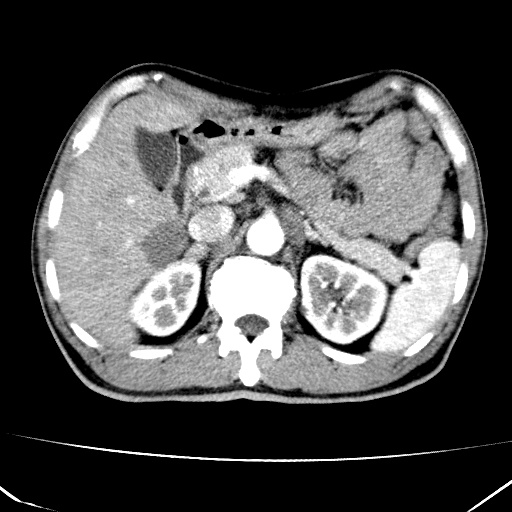

标题: CT17975:请求会诊。男、57岁。上腹部胀痛2天。临床诊断:糜 [打印本页]

标题: CT17975:请求会诊。男、57岁。上腹部胀痛2天。临床诊断:糜

肝脏多发类圆形低密度影,考虑肝脏转移瘤,肝胃韧带一淋巴结肿大,原发?胃癌?

考虑胃癌肝脏转移可能性大。

考虑胃癌并肝脏及腹膜后淋巴结转移;不排除淋巴瘤。

肝内转移瘤,腹腔及腹膜后淋巴结转移。